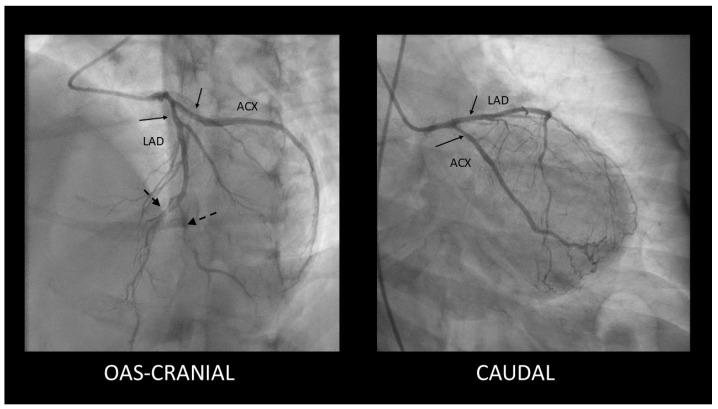

自发性冠状动脉夹层累及左主干并延伸至左前降支和左旋支:诊断与管理挑战

Spontaneous Coronary Artery Dissection Involving the Left Main with Extension to Left Anterior Descending Artery and Left Circumflex Artery: Diagnostic and Management Challenges.

Spontaneous coronary artery dissection is a rare cause of unstable angina, myocardial infarction, and sudden cardiac death, particularly among young women and individuals without conventional atherosclerotic risk factors. We present the case of a 43-year-old woman who had spontaneous coronary artery dissection involving the left main with extension to left anterior descending artery and left circumflex artery. She was ultimately managed medically, with a good outcome. Spontaneous coronary artery dissection is a unique and intricate condition that demands advanced diagnostic techniques and tailored management strategies. Greater awareness and advancements in imaging technologies have enhanced the detection and understanding of spontaneous coronary artery dissection. However, continued research is crucial to resolving outstanding uncertainties and optimizing patient outcomes.

摘要

自发性冠状动脉夹层是不稳定型心绞痛、心肌梗死和心源性猝死的罕见原因,尤其在年轻女性和无传统动脉粥样硬化危险因素的个体中。我们报告一例43岁女性患者,其发生自发性冠状动脉夹层,累及左主干并延伸至左前降支和左旋支。她最终接受药物治疗,效果良好。自发性冠状动脉夹层是一种独特且复杂的病症,需要先进的诊断技术和量身定制的管理策略。对成像技术的更多认识和进步提高了对自发性冠状动脉夹层的检测和理解。然而,持续研究对于解决悬而未决的不确定性和优化患者预后至关重要。